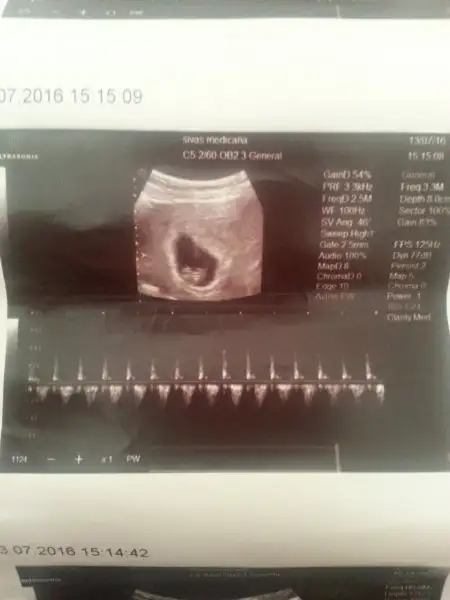

Bu arada karından ultrason ve kese sol tarafımdaydı

Karından canım İnşallah erkek bebek olur sağlıkla hayırla gelsin İNŞALLAH iki kızım var tabiki erkek evlatda tatmak istiyor insan öğrenince buraya yazarım Teşekkürler canımUsg karındansa erkek gibi,vajinalsa kız gibi